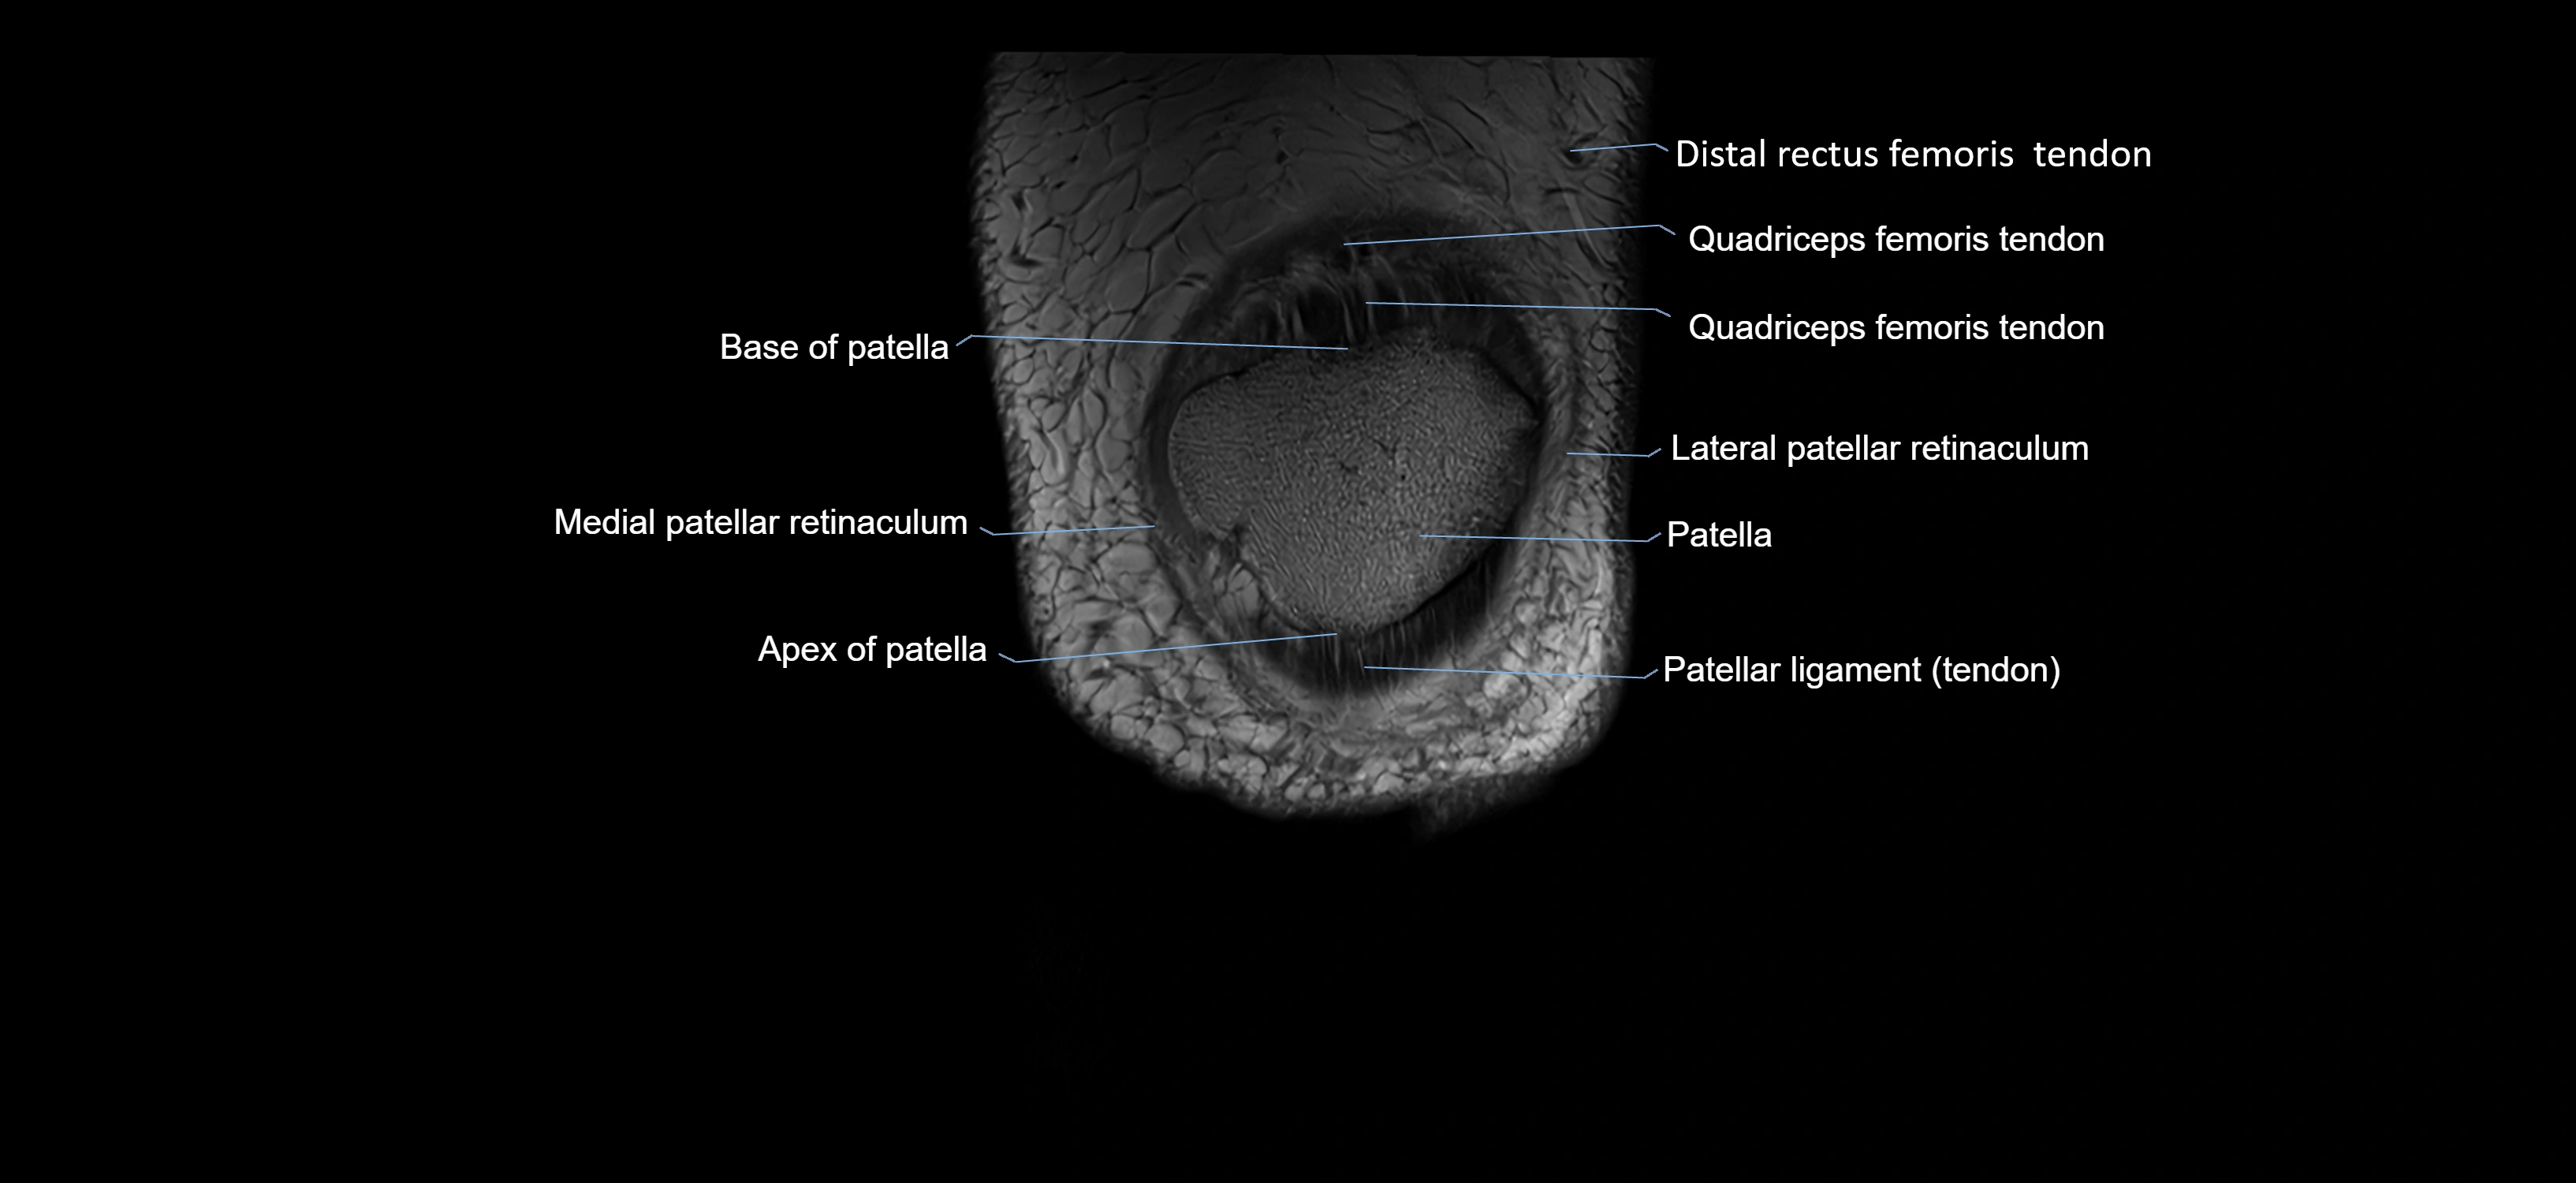

- Apex of patella

- Base of patella

- Distal quadriceps femoris tendon

- Distal rectus femoris tendon

- Lateral patellar retinaculum

- Medial patellar retinaculum

- Patella

- Patellar articular cartilage

- Patellar tendon (patellar ligament)